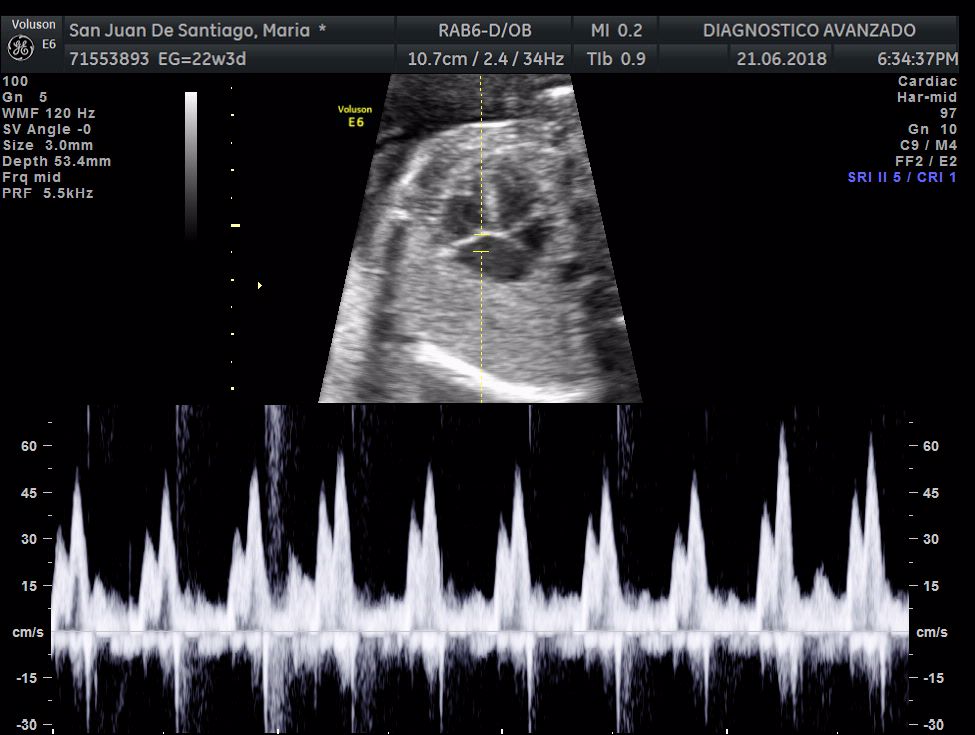

¡Hola a todos! Hoy hemos ido a hacer la tradicional ecografía 3D de la niña, os dejamos todo el material (aunque es un poco demasiado).